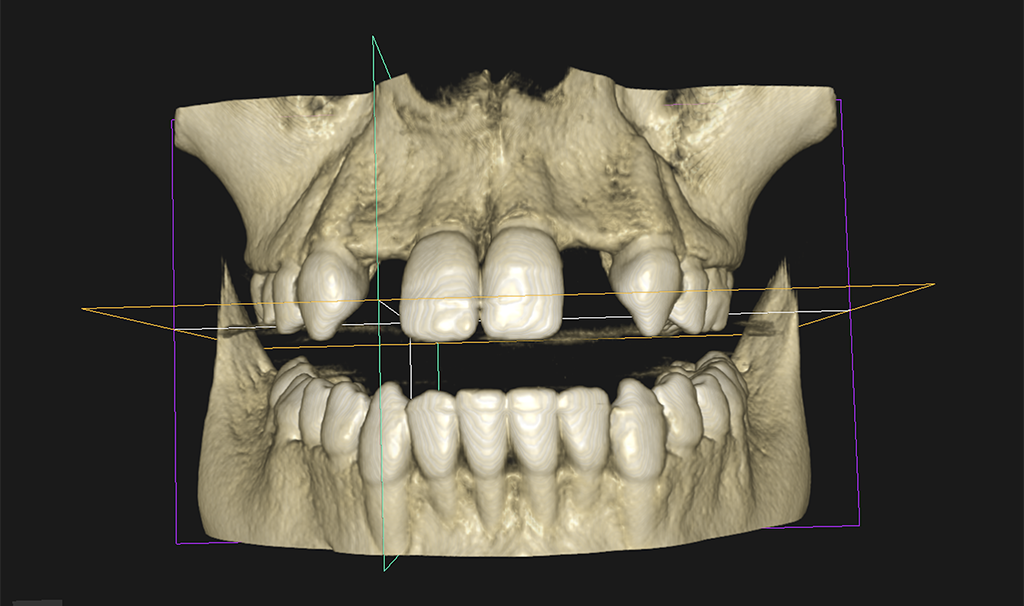

3D OPG

A panoramic radiograph is a panoramic scanning dental X-ray of the upper and lower jaw. It shows a two-dimensional view of a half-circle from ear to ear.